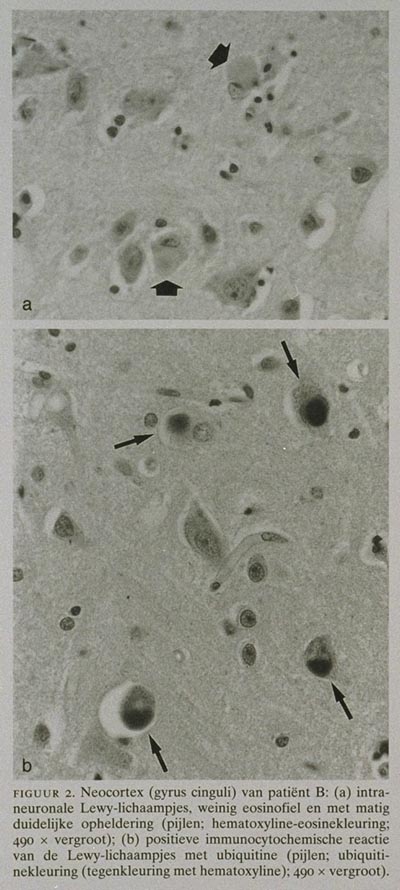

Patiënt overleed plotseling. Bij neuropathologisch onderzoek bleek dat de hersenen atrofisch waren. In de gepigmenteerde kernen van de hersenstam werden celverlies, gliose en Lewy-lichaampjes waargenomen. Deze Lewy-lichaampjes werden ook gevonden in de nucleus basalis van Meynert en bovendien in groten getale in de cortex, vooral in de gyrus cinguli (figuur 2). Seniele plaques en neurofibrillaire degeneratie waren niet aanwezig. De conclusie die uit de klinische en neuropathologische gegevens werd getrokken, luidde: ziekte van Parkinson met veel Lewy-lichaampjes in de grote hersenen, vooral in de gyrus cinguli. Er waren geen aanwijzingen voor de ziekte van Alzheimer.

Bij neuropathologisch onderzoek werd macroscopisch atrofie van de grote hersenen waargenomen. Microscopisch onderzoek toonde de kenmerken van de ziekte van Parkinson, te weten: celverlies, gliose en Lewy-lichaampjes in de gepigmenteerde kernen van de hersen

stam zoals de substantia nigra (figuur 1), de locus coeruleus en het ventrale tegmentum van het mesencefalon. Ook in de nucleus basalis van Meynert werden Lewy-lichaampjes gevonden. In de grote hersenen werden in de gyrus cinguli en de mediale temporaalkwab sporadisch enkele Lewy-lichaampjes geconstateerd. Deze corticale Lewy-lichaampjes kunnen in de conventionele hematoxyline-eosinekleuring gemakkelijk gemist worden.

De typische perifere opheldering (halo) ontbreekt nogal eens. Ze zijn echter fraai te kleuren met behulp van een immunocytochemische methode, waarbij gebruik wordt